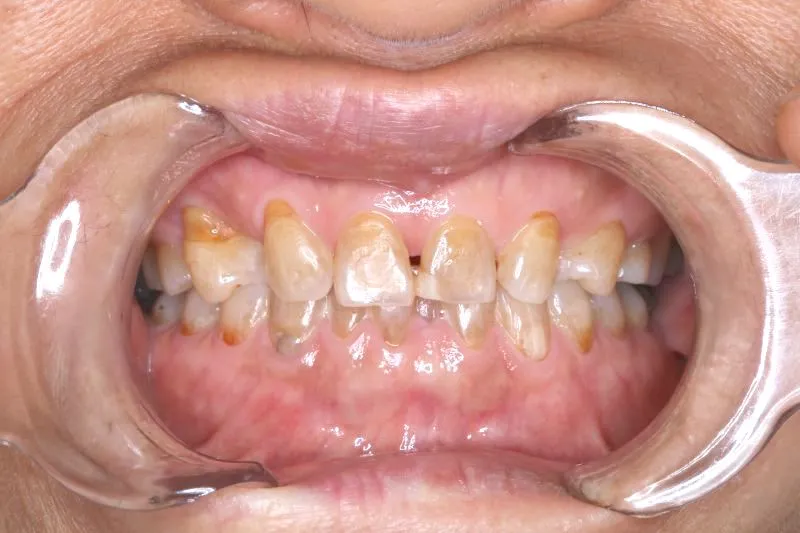

1.主訴 歯が足りない・ガタガタ

2.診断名あるいは主な症状 空隙歯列・先天性欠損歯

上の歯が2本足りないため上下のアーチが合わず、下の歯がガタガタになっています。

上下の幅をあわせ、噛み合わせから調整していきます。